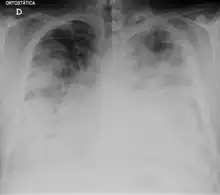

| Chest X-ray of a severe case of legionellosis upon admission to the emergency department | |

Laboratory tests may show that kidney functions, liver functions, and electrolyte levels are abnormal, which may include low sodium in the blood. Chest X-rays often show pneumonia with consolidation in the bottom portion of both lungs. Distinguishing Legionnaires' disease from other types of pneumonia by symptoms or radiologic findings alone is difficult; other tests are required for definitive diagnosis.